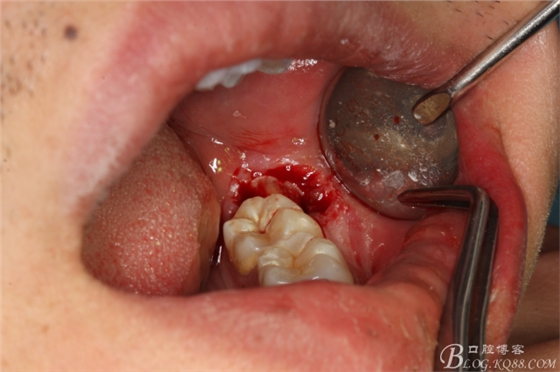

圖1.口內(nèi)觀:38牙冠萌出約1/3,頰側(cè)牙齦輕度紅腫,牙冠低于37合面,屬于中位阻生

圖4.采用不切開(kāi)、不翻瓣、利用暴露出來(lái)的牙冠進(jìn)行潛掘式分牙